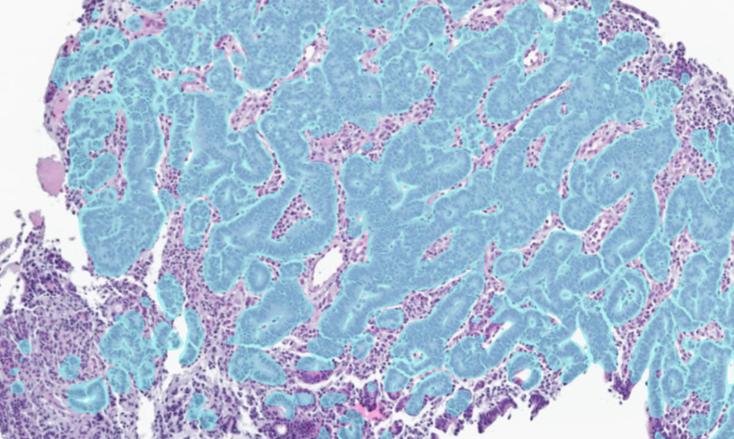

Aiforia® Gastric Suite uses AI to analyze digitized whole slide images to address these challenges. By highlighting suspicious areas directly on the slide, it enables efficient review while ensuring the pathologist remains in full control of interpretation and reporting.